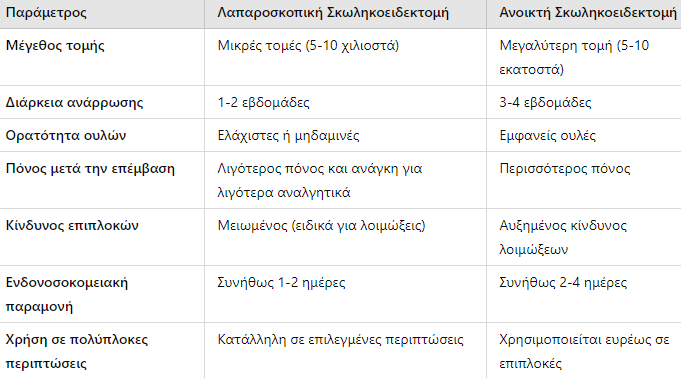

Σύγκριση Λαπαροσκοπικής με Ανοικτή Σκωληκοειδεκτομή